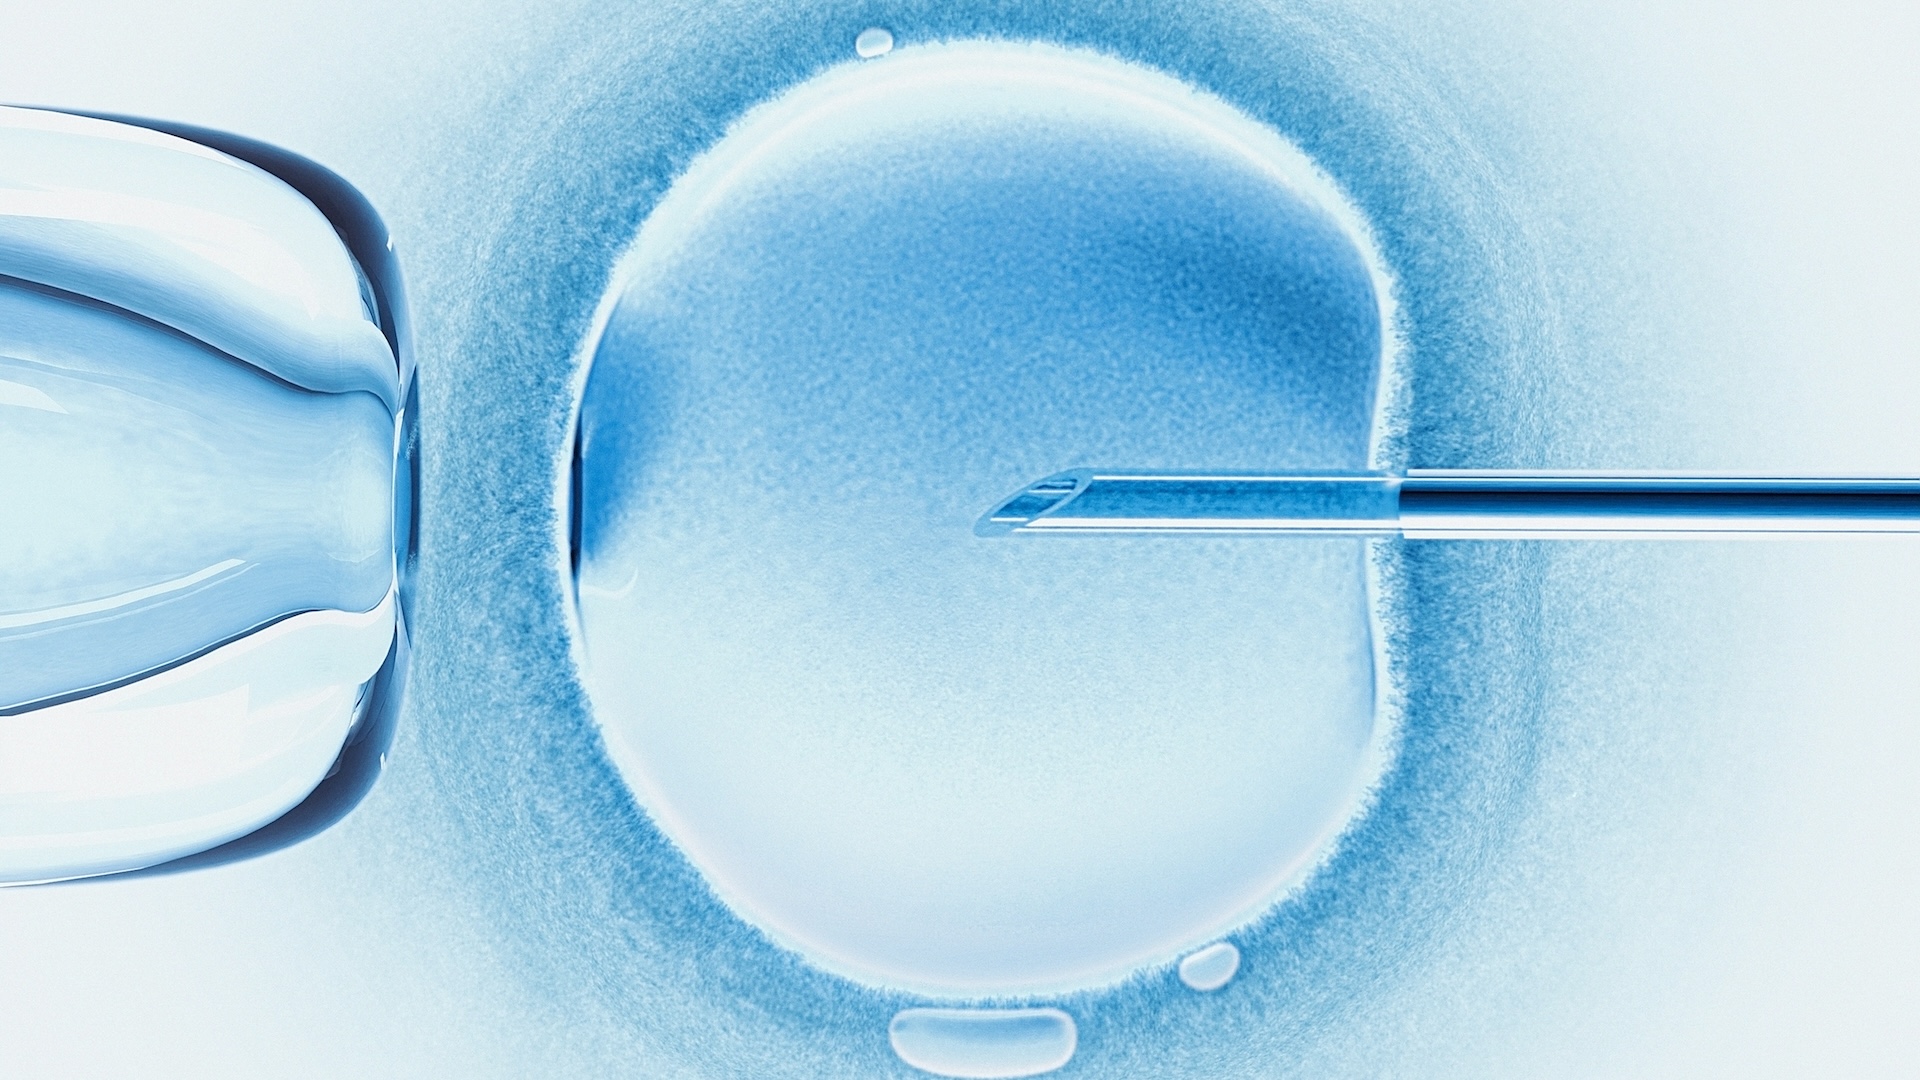

The bacteria, called Carnobacterium pleistocenium, might also be interesting to medical researchers.

"The enzymes and proteins it possesses, which give it the ability to spring to life after such long periods of dormancy, might hold the key to long-term, cryogenic -- or very low temperature -- storage of living cells, tissues and perhaps even complex life forms," Hoover said.